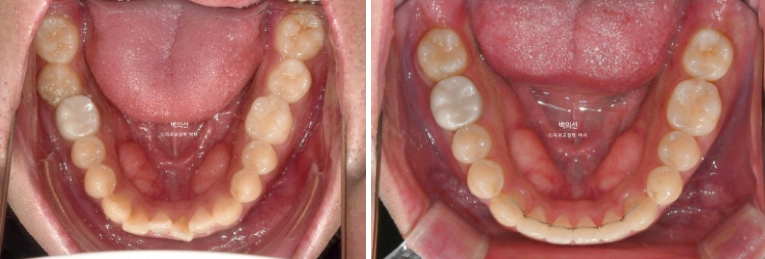

앞니가 삐뚤하고 소위 나비치아 입니다. 맨 뒤 큰어금니가 바깥으로 덧니처럼 뻗쳐있습니다.

교합면 사진에서 나비치아와 바깥으로 나가있는 두번째 큰어금니가 잘 보입니다.

24.01~24.07

치료시작 6개월차, 쓰러진 큰어금니가 서고 가위교합이 해소가 되었습니다.